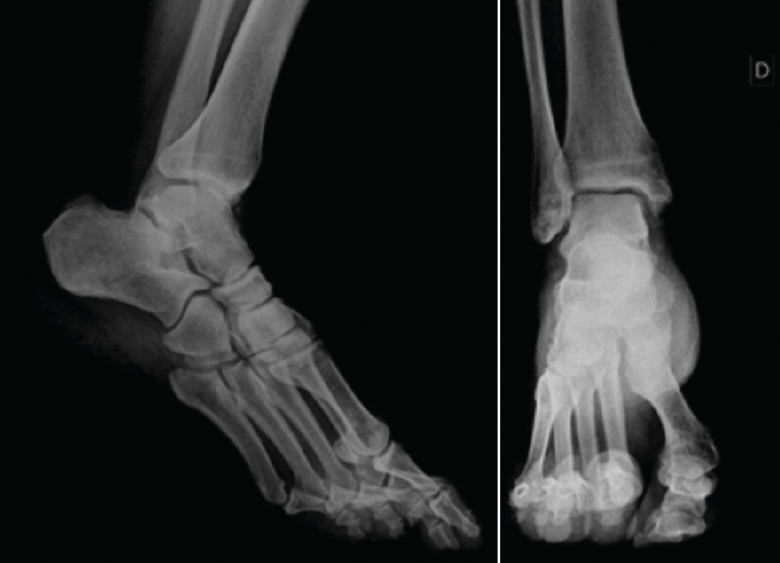

Se presenta el caso de un paciente varón de 54 años de edad, de profesión repartidor, que refiere una caída desde la plataforma de un camión, con torsión del tobillo derecho. Acude deambulando con la ayuda de un bastón. A la exploración física del tobillo derecho, presenta un balance articular disminuido con respecto al contralateral. Muestra dolor difuso a la palpación del ligamento peroneoastragalino anterior y posterior, y en la cúpula astragalina en la cara anterior del tobillo. No presenta dolor a la compresión de la sindesmosis. No da impresión de inestabilidad con maniobras de varo/valgo. En la radiografía se descartan fractura o signos indirectos de lesiones de partes blandas (Figura 1).

Figura 1. Radiografía anteroposterior y lateral del tobillo derecho.